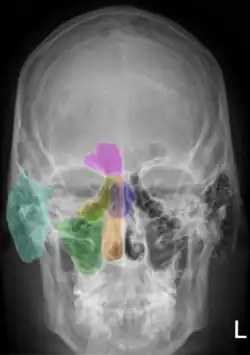

Рентгеноанатомия

Рентгеноанатомия (рентгеновская анатомия) — теоретическая дисциплина на стыке анатомии и рентгенологии, изучающая структурные закономерности рентгенографических изображений тела человека. Индивидуальные и возрастные рентгеноанатомические варианты строения рассматривает клиническая рентгеноанатомия. Функциональные особенности анатомических структур изучаются функциональной рентгеноанатомией.

Выделение рентгеноанатомии, как самостоятельной анатомической дисциплины, обусловлено характером получения изображения внутренних структур организма при рентгенографии. Рентгеновский снимок представляет собой двухмерное изображение трёхмерного объекта, что сопряжено с проекционным наслоением различных анатомических структур; это требует наличия определённых навыков для корректной трактовки подобных изображений. С учётом возможностей рентгенографии, выделяют рентгеноанатомию костей скелета, органов грудной клетки, других внутренних органов (пищеварительной, сердечно-сосудистой, мочеполовой систем и др.).